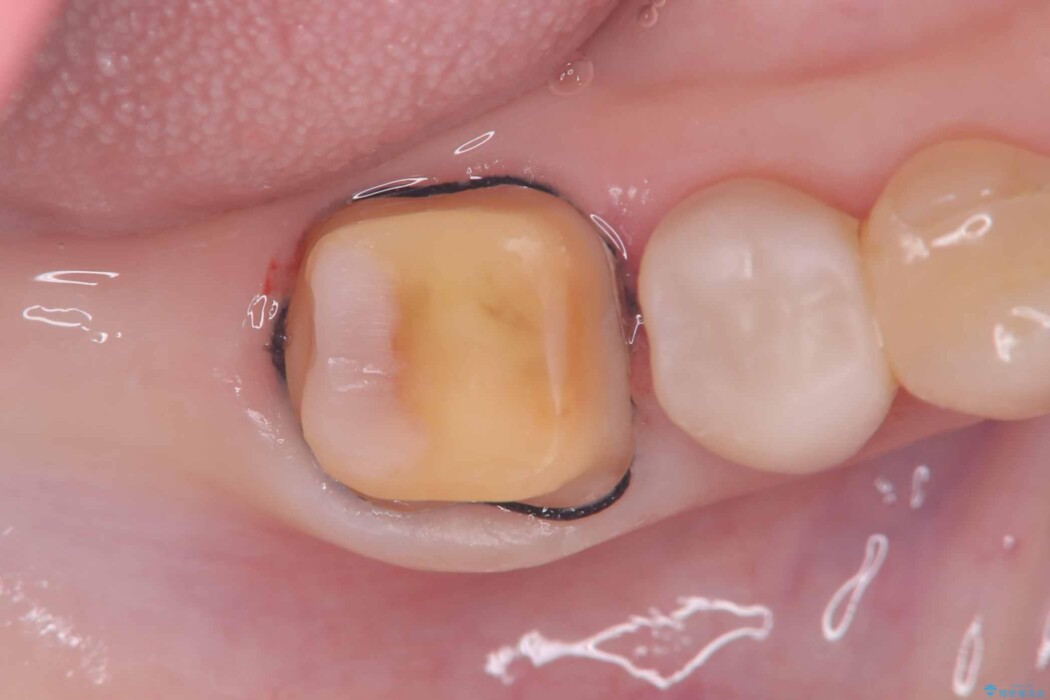

破折の再発防止および歯質保護を最優先に考え、オールセラミッククラウンによる治療を計画しました。

歯の中央から両側にかけて大きく削られている(MOD窩洞)状態でした。

このようなケースでは、部分的に詰める治療よりも歯全体を覆うクラウンの方が強度的に有利です。

そのため今回は、歯をしっかり保護し、長期的な安定を図るために、オールセラミッククラウンによる修復を行いました。